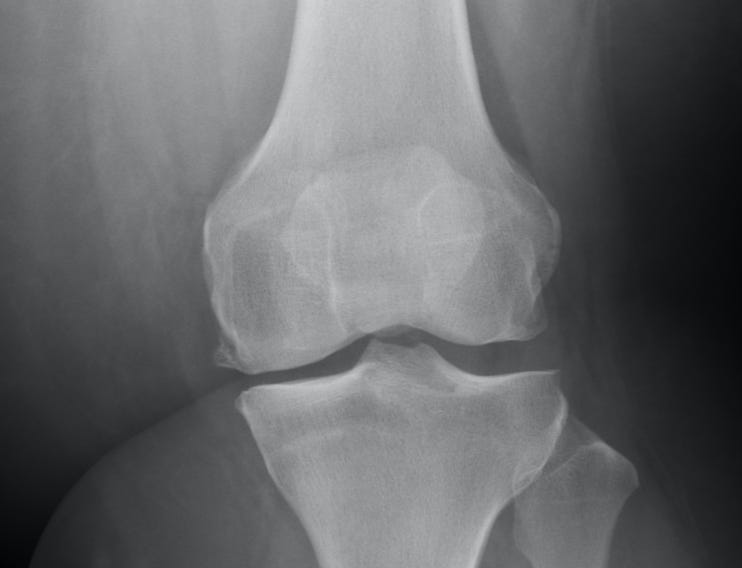

By this time both of my knees were bone-on-bone, what little cartilage I had left looking like shredded fabric in my x-rays. I could have gotten down to my birth weight and I’d still be in pain.

And so I dug up the information from Marilyn Wann that I’d stashed a year earlier, and I made an appointment with a doctor in Chicago. I waited six weeks for an appointment where I was immediately given x-rays—something only one ortho had bothered to do for me—and told, “Yep. You need a full knee replacement. Because of your weight, your risk for infection is one to one and a half times higher than average. Cool? Cool. Let’s get you on the schedule.”

Okay, it was a bit more involved in that, but my point is, he looked at my x-rays, saw what I needed, and provided. I didn’t have to prove I was in pain. I didn’t have to fight for myself. After years of fighting to be heard, I can now rest.